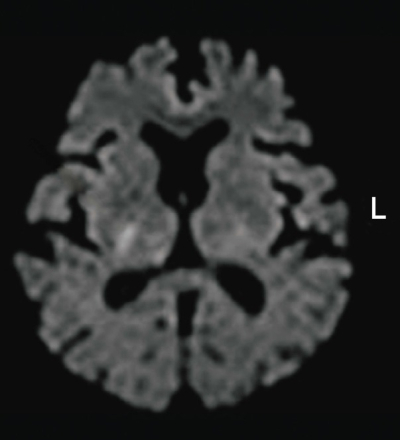

検査所見:血液所見:赤血球 491 万、Hb 15.2 g/dL、Ht 46 %、白血球 6,300、血小板 26 万。血液生化学所見:総蛋白 7.2 g/dL、AST 26 U/L、ALT 28 U/L、尿素窒素 11 mg/dL、クレアチニン 0.9 mg/dL、トリグリセリド 240 mg/dL、HDL コレステロール 46 mg/dL、LDL コレステロール 100 mg/dL。来院時の頭部 MRI の拡散強調像を別に示す。